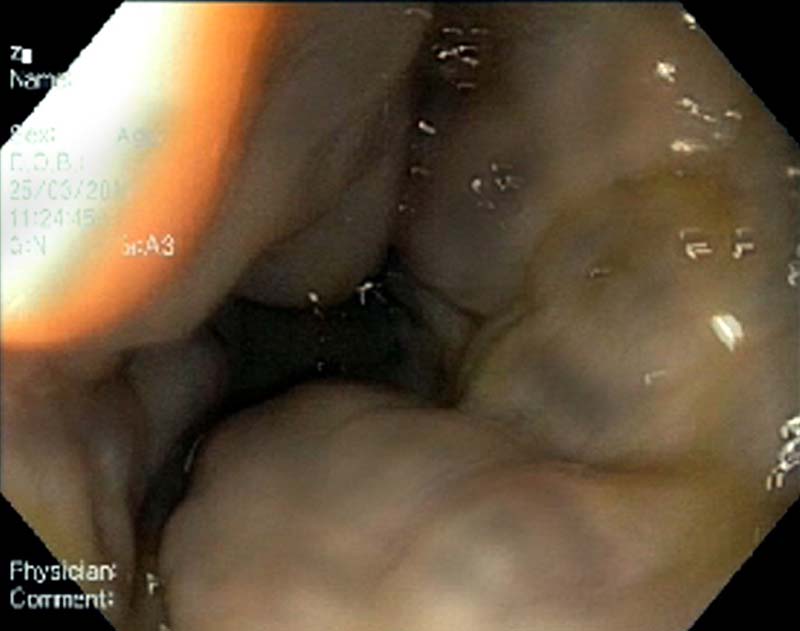

Наряду с неспецифическими проявлениями, важными клиническими симптомами являются спленомегалия (нередко достигающая гигантских размеров), а также симптомы анемии и/или гипербилирубинемии (при их наличии). [20] Набор инструментальных методов исследования, так же как и в случае ОТВВ, включает в себя УЗДГ, КТ или МР-ангиографию, ЭГДС. Последняя обнаруживает ВРВ пищевода и желудка, при этом они часто имеют большой диаметр и распространяются на весь пищевод (рис. 2), начиная от его верхней трети; переходят на кардию, тело и дно желудка (рис. 3). [6, 7, 10, 13, 14, 25, 44, 50] Наличие эктопических ВРВ (в двенадцатиперстной кишке, аноректальной зоне, ложе желчного пузыря) более характерно для данной группы пациентов, чем для больных ЦП. [53, 54]

Рис. 3. Эндоскопическая картина ВРВ желудка при тромбозе воротной вены.